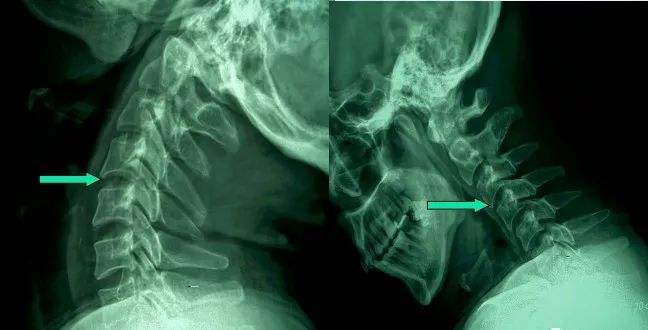

1、頸椎移位

由于頸椎關(guān)節(jié)突間關(guān)節(jié)面近乎水平位,一旦椎間盤(pán)發(fā)生退變、椎間隙即變窄,關(guān)節(jié)囊及韌帶松弛,加上頸部活動(dòng)時(shí)重力的影響,即可造成積累性損傷,加速頸椎退變和不穩(wěn),導(dǎo)致頸椎關(guān)節(jié)發(fā)生移位,使椎間孔變狹,椎管徑發(fā)生改變,壓迫神經(jīng)根或脊髓,產(chǎn)生臨床癥狀與體征。